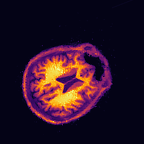

Multi-modality (or multi-channel) imaging is becoming increasingly important and more widely available, e.g. hyperspectral imaging in remote sensing, spectral CT in material sciences as well as multi-contrast MRI and PET-MR in medicine. Research in the last decades resulted in a plethora of mathematical methods to combine data from several modalities. State-of-the-art methods, often formulated as variational regularization, have shown to significantly improve image reconstruction both quantitatively and qualitatively. Almost all of these models rely on the assumption that the modalities are perfectly registered, which is not the case in most real world applications. We propose a variational framework which jointly performs reconstruction and registration, thereby overcoming this hurdle. Numerical results on simulated and real data show the potential of the proposed strategy for various applications in multi-contrast MRI, PET-MR, and hyperspectral imaging: typical misalignments between modalities such as rotations, translations, zooms can be effectively corrected during the reconstruction process. Therefore the proposed framework allows the robust exploitation of shared information across multiple modalities under real conditions.

翻译:多模式(或多通道)成像越来越重要,而且越来越普及,例如遥感中的超光谱成像、材料科学中的光谱CT以及医学中的多调MRI和PET-MR等,过去几十年的研究产生了大量数学方法,将多种模式的数据结合起来。通常作为变异性正规化的先进方法表明,在数量和质量上都大大改进了图像重建。几乎所有这些模型都基于这样一种假设,即模式已经完全登记,而在大多数现实世界应用中情况并非如此。我们提议了一个变通框架,共同进行重建和登记,从而克服这一障碍。模拟和实际数据的数字结果显示,拟议的多调MRI、PET-MR和超光谱成像的各种应用战略具有潜力:在重建过程中可以有效地纠正诸如轮换、翻译、缩影等模式之间的典型的不匹配。因此,拟议的框架允许在现实条件下,在多种模式中大力利用共享的信息。